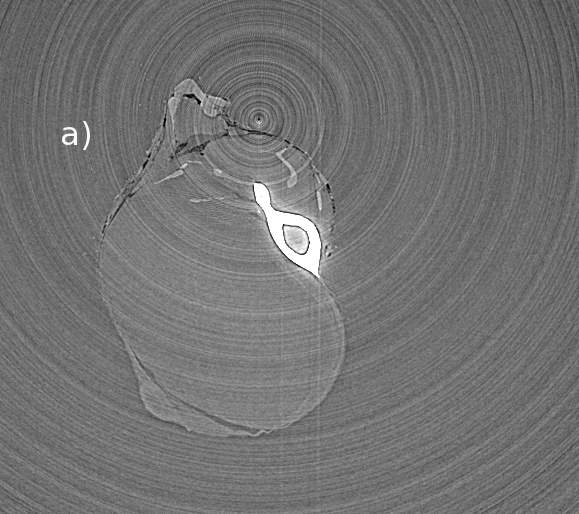

The last preprocessing step is performed on the sinograms to reduce the so-called ring artifacts. These artifacts are due to residual errors which are linked to a given pixel that still remain in the treated data even after applications of flat-field corrections and hot-spots removal filter. These errors are visible in the sinogram as features which are parallel to the projection-angle axis and give raise, in the reconstructed slice, to ring-shaped artefacts. An optional filter can be used for these features. The filter reduces first the sinogram to a 1D signal by summing over the projection-angles. An high-frequencies filter is then applied in an attempt to extract these features and the result is subtracted from the sinogram. This approach can give satisfactory results but, in some cases, new artefacts can appear if the filtered signal contains a part coming from the sample. We show in figureΒ 1a(left) a tomographic slice of a mouse leg with no corrections for the ring artefacts. We have applied the ring corrections for figureΒ 1b(center). This corrects well the ring artefacts but new artefacts appear which are linked to the sample, not to the detector. In particular to the leg bone which has a strong absorption and sharp borders. PyHST2 can treat this problem by thresholding the bone in a first reconstructed slice. The thresholded signal is then subtracted to the data before application of the high-pass filter. The result is shown in figureΒ 1c(right).

Figure 1: Rings correction on a mouse leg tomography slice : a) with no corrections residual pixel-based errors give concentrical ring artefacts. b) the application of the rings correction filter removes the rings but new introduces artefacts which are due to the bones. c) a pro-filter thresholding treatement of the bone suppresses the new artefacts.